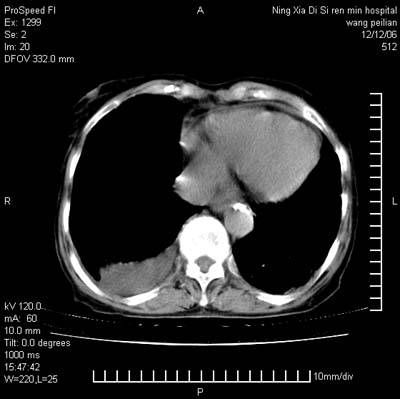

标题: CT5609:胸部:女77 病史不详 [打印本页]

标题: CT5609:胸部:女77 病史不详

两肺可见多个大小不等的结节,左侧有胸水,纵隔淋巴结增大,考虑是细支气管肺泡癌

两肺尖纤维索状影,两下肺结节块状影,且有钙化灶,右胸腔积液。考虑肺结核并胸膜炎。

双侧肺结核伴右侧胸腔积液.

两肺尖纤维索状影,两下肺结节块状影,且有钙化灶,右胸腔积液。考虑肺结核并胸膜炎肺间质纤维化